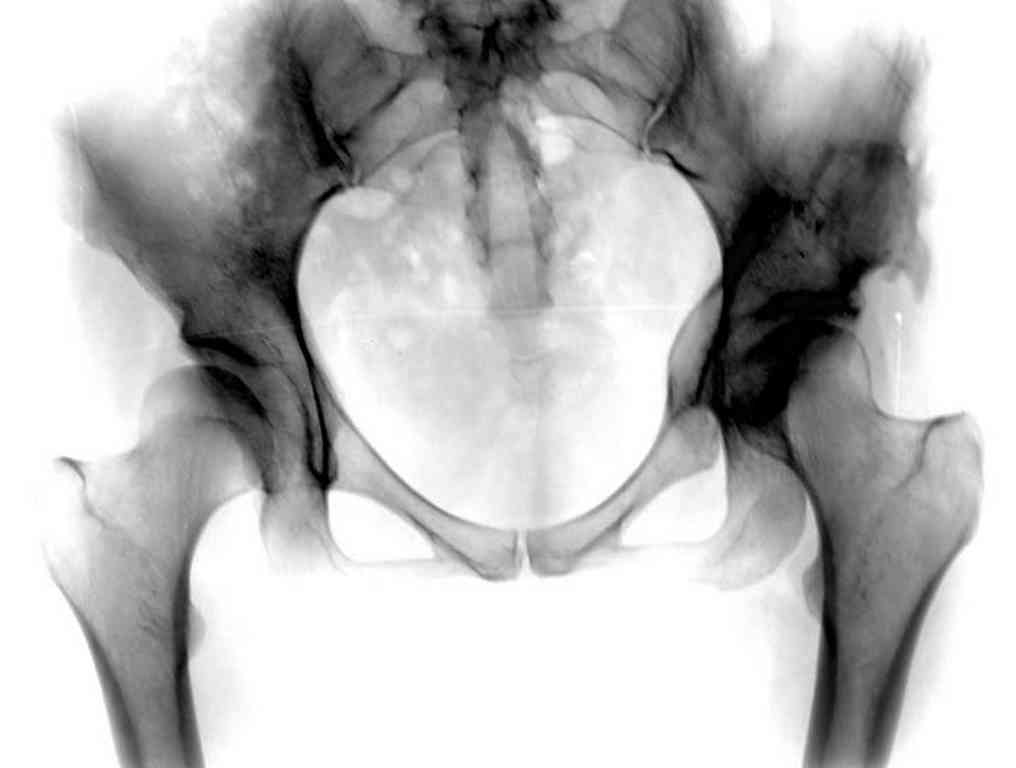

Вложение не в текстовом формате было извлечено…

Имя     : Displasia PostOp.jpg

Тип     : image/jpeg

Размер  : 34861 байтов

Описание: отсутствует

Url     : http://weborto.net:8080/pipermail/ortho/attachments/20101217/2fe082a4/attachment-0004.jpg

Типичная концовка проигнорированного диспластического состояния сустава. Дисплазия тазобедренного сустава часто встречающаяся патология у жителей Центральной Азии вследствие тугого пеленания в детстве. Традиционно ребенок находится в течение дня в так называемой кроватке "бешик", удобной в быту, но она впоследствии приводит к недоразвитию тазобедренного сустава.

При более сохранном суставе от дальнейшего разрушения можно было бы сохранить только периориентацией нагрузки на сустав - Периацетабулярной Остеотомией .